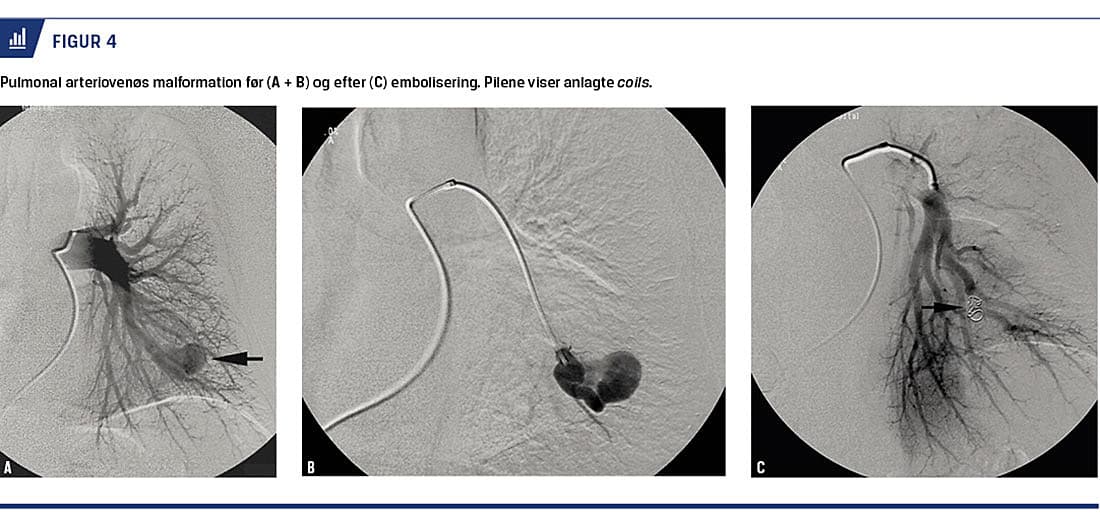

Torakale endoproteser (TEVAR) kan anlægges stadigt mere proksimalt i aorta enten med proteser med sidegrene eller i hybridkombination med kirurgisk transposition af de brakiocefale arterier, således at også nogle dissektioner og aneurismer, der medinddrager arcus, kan behandles endovaskulært. Ved traumatisk aortaruptur (Figur 1) er mortaliteten efter TEVAR nedbragt til under 10%, så hvis det er teknisk og logistisk muligt, er TEVAR førstevalget til patienter med traumatisk aortaruptur.